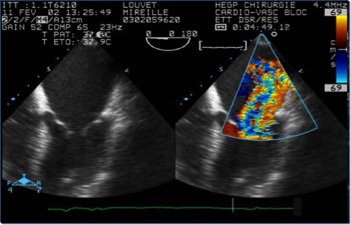

Insufficienza mitralica di tipo I, dovuta a dilatazione anulare e relativa immagine all’eco-colordoppler

L’area del jet di rigurgito, esaminata al color-doppler , è uno dei parametri più usati, soprattutto quando espressa in rapporto all’area dell’atrio sinistro.

Il diagramma mostra la valutazione della severità dell’insufficienza mitralica usando l’approccio transesofageo con vista asse-lungo. La gravità dell’insufficienza mitralica (1-4+) viene stabilita in base alla lunghezza e alla larghezza del flusso di jet nell’atrio sinistro. LA, atrio sinistro.; RV, ventricolo destro; LV, ventricolo sinistro.